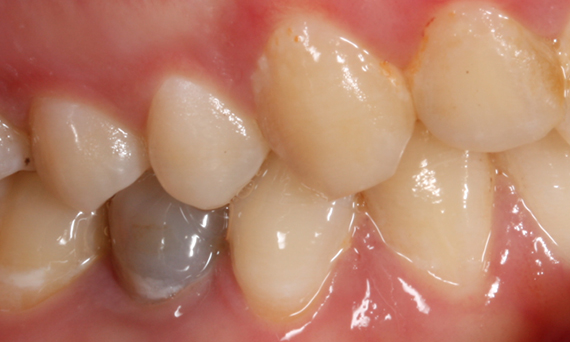

Before

First upper molar had been restored with an extensive yet insufficient composite filling that already showed visible fractures.

After

Chairside-fabricated restoration made from an advanced lithium disilicate ceramic, CEREC Tessera.